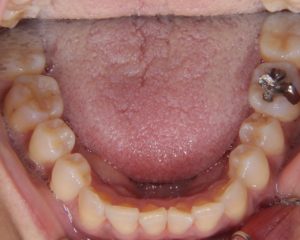

今回の症例は開咬・叢生です。

今回の症例紹介は正中のずれを伴った叢生の非抜歯の治療です。初診 ①主訴 前歯のガタガタ②診断名 叢生③年齢18歳④治療に用いた主な装置 マルチブラケット装置 歯科矯正用アンカースクリュー⑤抜歯部位 な...記事を読む